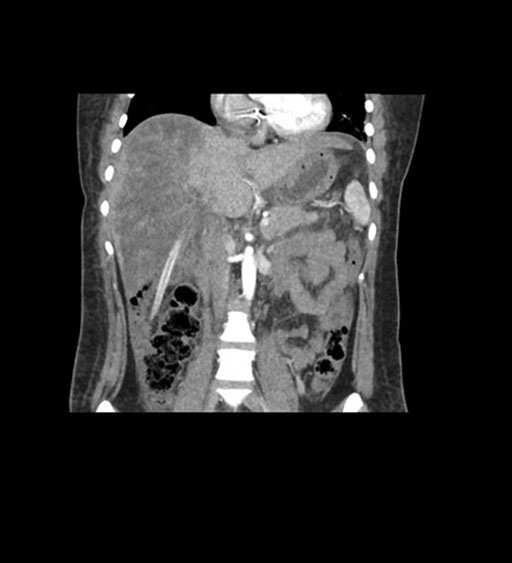

Imaging Analysis

Look through the patient's CT scan to identify any areas of concern for the necessary procedure.

Coronal Arterial

Coronal Venous

Based on initial findings, which issue(s) would you be most concerned about?